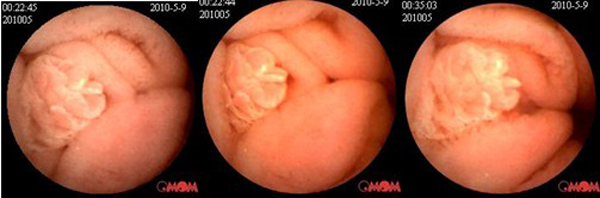

胶囊内镜拍到的小肠息肉